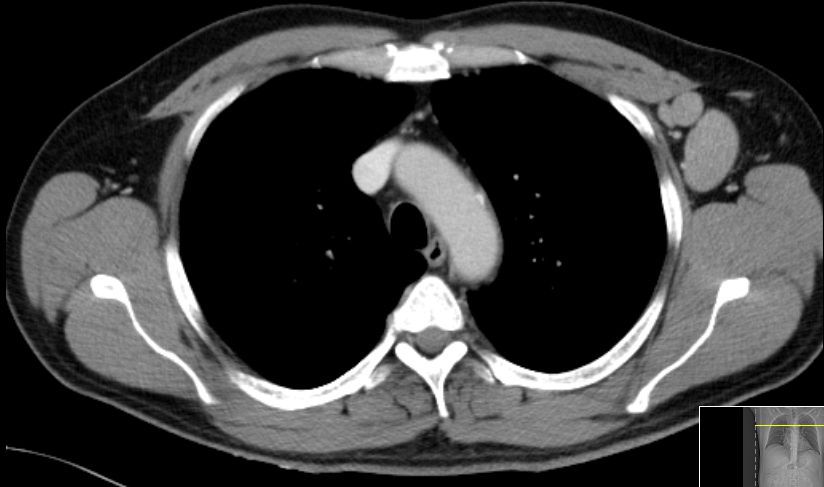

| thorakal | 21-jährige Frau mit Morbus Hodgkin mediastinal und zervikal beiderseits. Stadium IIA, Risikofaktor: hohe BSG. Noduläre Sklerose. | ||